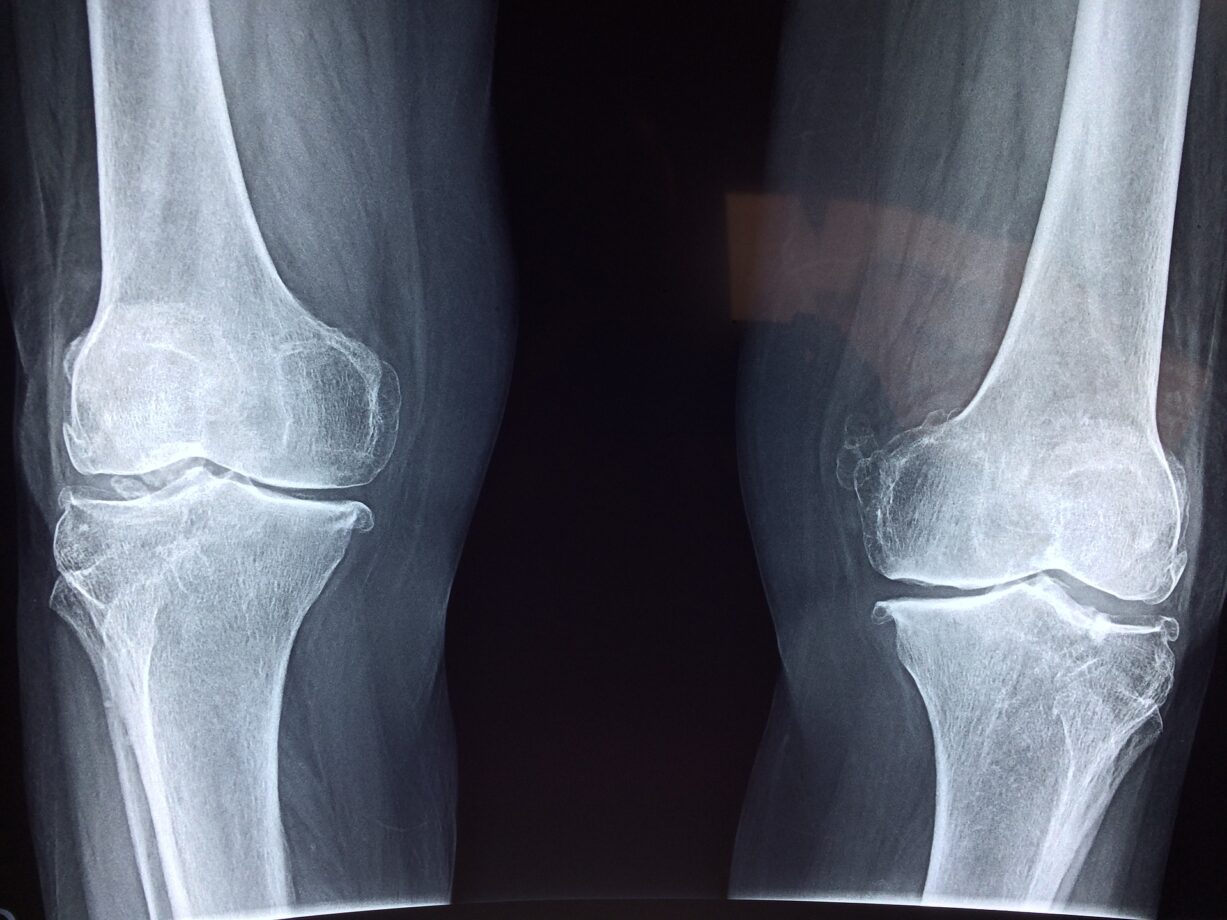

Il ginocchio è una parte del nostro corpo in cui potremmo sentire dolore anche senza un motivo apparente. Continuamente sotto sforzo, sono sopratutto le persone sportive a sentire in alcuni casi anche dolori giornalieri. Vediamo insieme quali possono essere le cause di questo dolore e in che modo possiamo intervenire.

Ci sono diverse lesioni o malattie che possono colpire la zona causandoci dolore. Diverse patologie causano dolore in diversi punti della zona, per esempio laterali o posteriori. Delle cause possono essere: